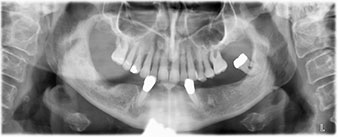

Die 64-jährige Patientin wurde mit einer Unterkiefer-Restbezahnung 38, 33 und 43 und einer klammerbefestigten Interimsprothese im Unterkiefer vorstellig (Abb. 1 und 2).

Abb. 2

Zur Planung und Risikominimierung wurde eine dreidimensionale Volumentomografie (DVT, Planmeca) erstellt. Dieses zeigte, dass die Qualität und Quantität des Knochens für eine Operation und Sofortversorgung nach der Fast & Fixed-Methode ausreichend war. Nach Protokoll dieses Konzeptes wird in Regio 35, 32, 42 und 45 implantiert. Durch die bis zu 45-Grad-Schiefstellung der distalen Implantate wird das Durchtrittsprofil nach posterior verlegt und ein größeres Stützpolygon erreicht (Abb. 3).